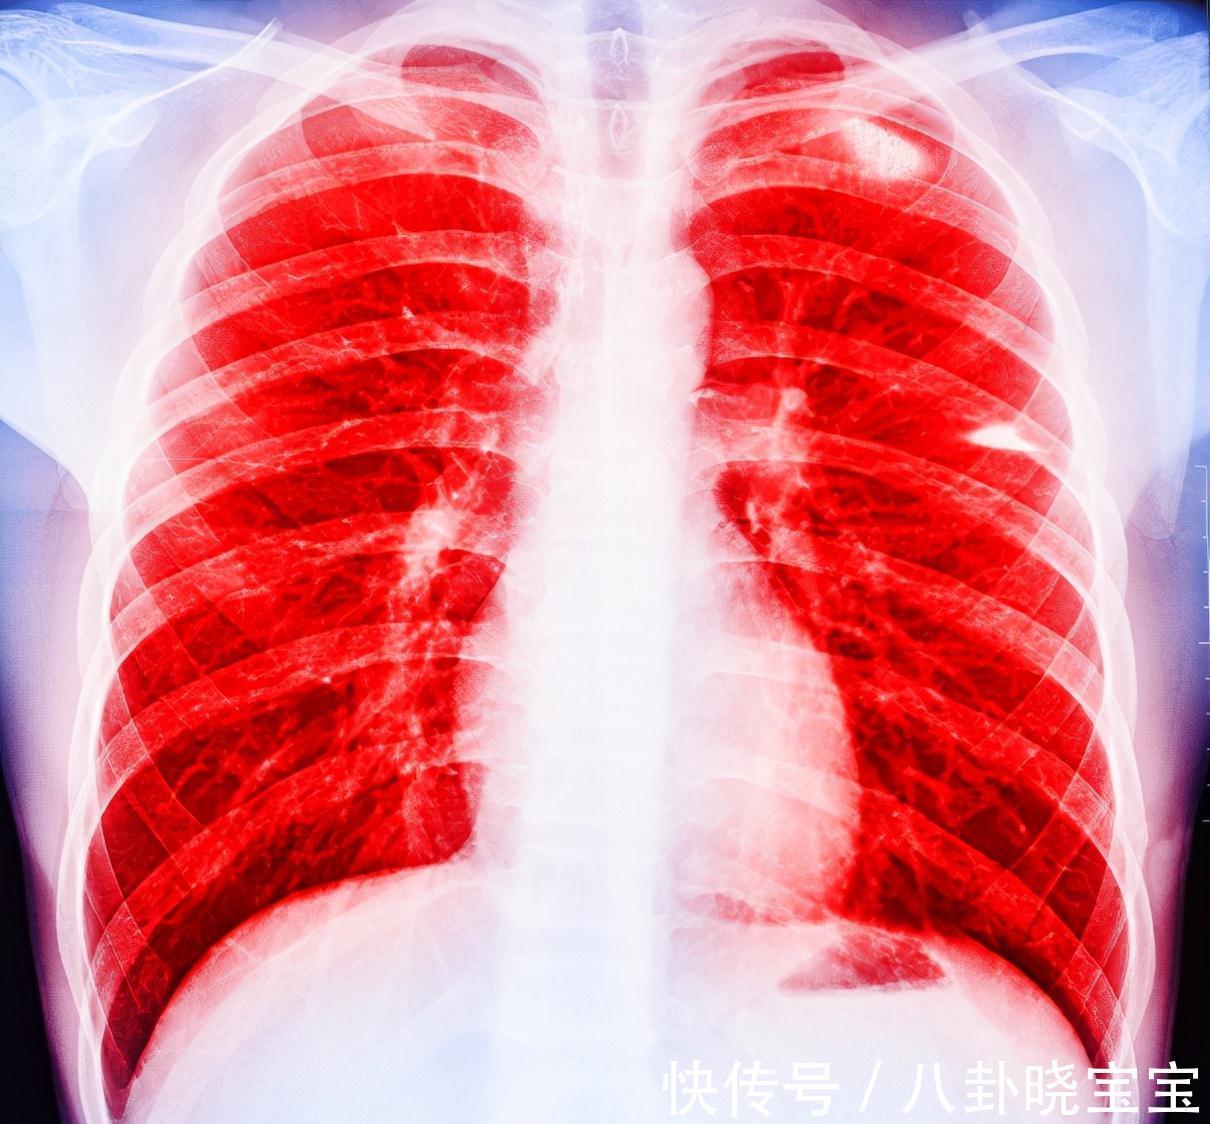

想要避免重蹈小吴的覆辙,该如何早点发现肺癌呢?记住下面这几种症状

1、出现持续性的干咳,这种情况在夜晚睡觉的时候最为明显,小吴母亲最初的症状就是如此。如果出现了这种症状,一定要引起重视,如果当你发现咳出的痰里发现了血丝的话,可能为时已晚了。

2、夜间失眠或者突然地惊醒,当人的肝脏和肺部出现了问题后,很容易就会将在夜间突然醒来,出现了这种情况,可能是肺在提醒你它出了问题。

3、睡觉时胸背部疼痛,癌细胞会压迫到周围组织,引起胸背部疼痛,这种疼痛在夜晚睡觉的时候会特别明显。

4、睡觉时出现呼吸不畅,多是肿瘤阻塞了气管导致的,身体躺下以后,这种情况会加剧,但是要注意的是,不是所有的睡觉时引起的呼吸困难都是肺癌,像心衰与肺水肿等都会导致呼吸困难。